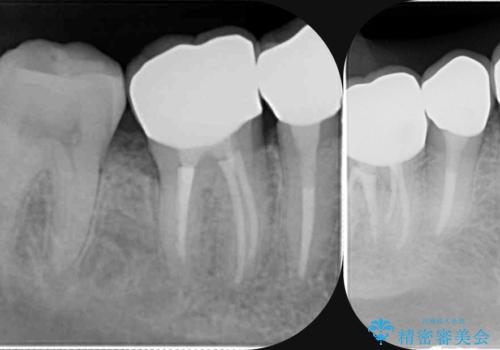

- 放置してしまった虫歯治療を希望され来院されました。

虫歯を徹底的に除去したのち、長期的に安定し審美的なジルコニアクラウンで機能回復を図ります。

- 35万円(仮歯・ファイバーコア・ジルコニアクラウン×3)費用は治療当時の料金となります